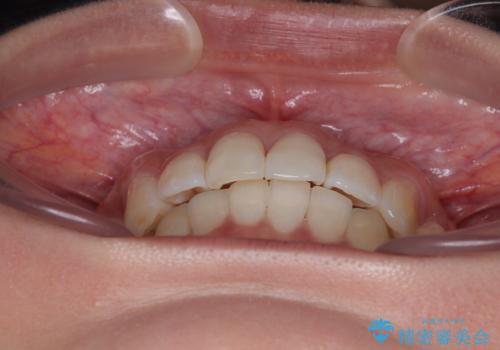

前歯のデコボコを治したい インビザライン矯正

- 上下前歯の叢生を気にして来院された患者様です。

インビザラインでの治療を希望されていて、デコボコの程度が中等度であり、安価なパッケージにて対応可能と判断されたため、インビザライン・モデレートを用いて矯正治療を行うこととしました。